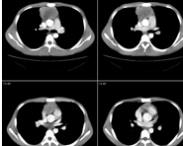

• 心包胸腺瘤

628健康網為您分享有關心包胸腺瘤的癥狀,心包胸腺瘤的治療方法,心包胸腺瘤的預防知識,心包胸腺瘤的癥狀圖片,心包胸腺瘤...